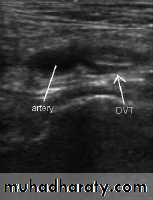

Doppler ultrasonography

Duplex US with color-flow imaging (sometimes called triplex ultrasound):This is a special type of 2-dimensional ultrasound that uses Doppler-flow information to add color for blood flow in the image. Vessels in the blood are colored red for flow in one direction and blue for flow in the other, with a graduated color scale to reflect the speed of the flow.

Duplex ultrasonography , due to its high sensitivity , specificity and reproducibility , has replaced venography as the most widely used test in the evaluation of DVT.